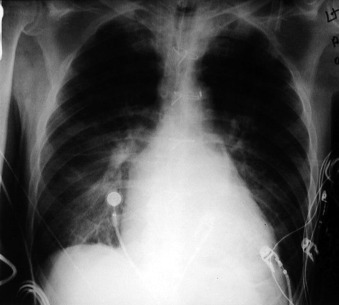

Pulsatile Devices: Intra-aortic Counterpulsation Balloon ( Figs. 24-1 to 24-7 )

The tip of an intra-aortic balloon (which is highly visible because of its metallic marker) should be at least 4 cm below the “knuckle” of the aorta (i.e., below the left subclavian artery). The balloon appears as a cylindrical lucency if the radiographic exposure happened to be while it was inflated in diastole. Widening or haziness of the aorta suggests aortic dissection as a complication of the catheter. Incorrect insertion into the inferior vena cava is suggested by the shadow of the catheter lying to the right of the patient’s vertebral column.